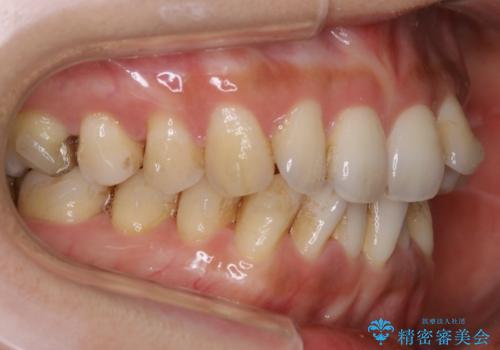

- 歯のガタつきによる見栄えや清掃困難を主訴にご来院されました。

左側の噛み合わせは上の歯が前方に寄ってきてしまっていることが原因のズレがありました。

ガタつき自体は歯列の幅の拡大やディスキング(IPR)でほとんど解消可能でしたが、噛み合わせのズレは歯の移動が必要だったため、左上にマイクロインプラントを使用し噛み合わせの改善とガタつきの解消を同時に進めるという方針をとりました。